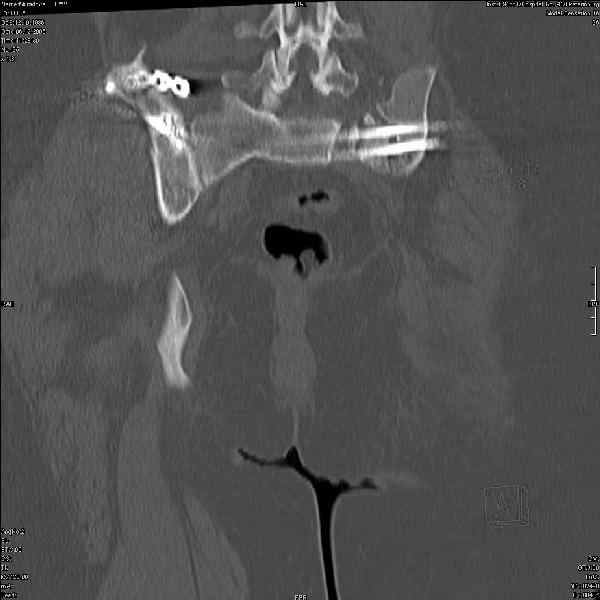

Молодая девушка 19 лет, травма 1 год назад, тогда же прооперирована.

В настоящее время имеются ноющие боли в области крестца слева, нарушение походки, ощущение неуверенности, слабости в левой нижней конечности, неврологически -непостоянные парестезии в левой нижней конечности. Ходит с дополнительной опорой, страдает от ожирения.

В приложении снимки при поступлении и послеоперационные год назад.

Могу сказать одно: миграция винтов и нестабильность синтеза левого подвздошно-крестцовогоо сочленения очевидна.

были использованы винты 7.2 мм, кроме того иетодика транссакральной фиксации не является общепринятой и широко рекомендуемой, но и в этих случаях они наблюдали случаи вторичного смещения

Забыл добавить, что ИХМО показан реостеосинтез более длинными винтами, с более широкой резьбой, с фиксацией за правое подвдошно-крестцовое сочленение.